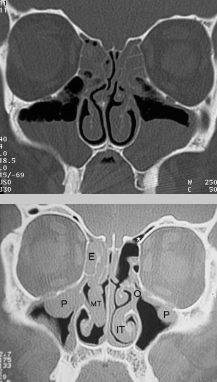

sinusitis (image demonstrates chronic sinusitis as mucosal lining has gotten polyp-like, thus no visualization of air-fluid levels)

What pathology is pictured here?

nasal polyps from chronic sinusitis